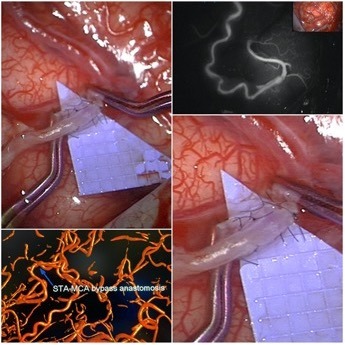

Zerebraler Bypass